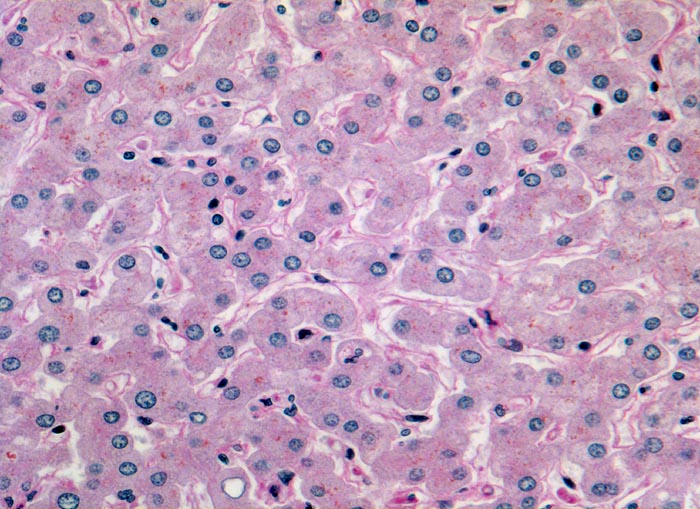

Makroskopisch imponiert das hepatozelluläre Karzinom als solitäre grosse Tumormasse, als zahlreiche zirrhoseartige Knoten oder als scharf begrenzter Knoten mit oder ohne Kapsel. Die tumorfreie Leber ist in der Mehrheit der Fälle zirrhotisch umgebaut. Mikroskopisch bilden die Tumorzellen mehr als 2 Zellen breite Trabekel (> 1237), kompakte Tumormassen (> 1229) oder pseudoglanduläre Strukturen (dilatierte Canaliculi) (> 1212) (> 1199). Desmoplastisches Bindegewebe fehlt meist. Innerhalb des Tumors fehlen Portalfelder. Es finden sich lediglich Arterien. Etwa bei der Hälfte der Karzinome lässt sich intrazytoplasmatische oder intracanaliculäre Galle (> 1238) nachweisen. Immunhistochemisch lassen sich mit einem polyklonalen Antikörper gegen Carcinoembryonales Antigen (CEA) Gallecanaliculi zwischen den Tumorzellen nachweisen. Die Tumorzellen bilden keinen Schleim.

• Die Tumorzellen bilden Trabekel, welche überwiegend mehr als 2 Zellen breit sind und Pseudodrüsen.

• Sinusoidartige Blutgefässe mit Endothelauskleidung verlaufen zwischen den Trabekeln und den Pseudodrüsen.

• Die Tumorzellen erinnern an normale Hepatozyten, sind aber kleiner als die Hepatozyten und die Kern-Zytoplasmarelation ist deutlich erhöht. Das Zytoplasma ist basophiler als das der angrenzenden Hepatozyten.

• Galle ist sichtbar in den Pseudodrüsen.